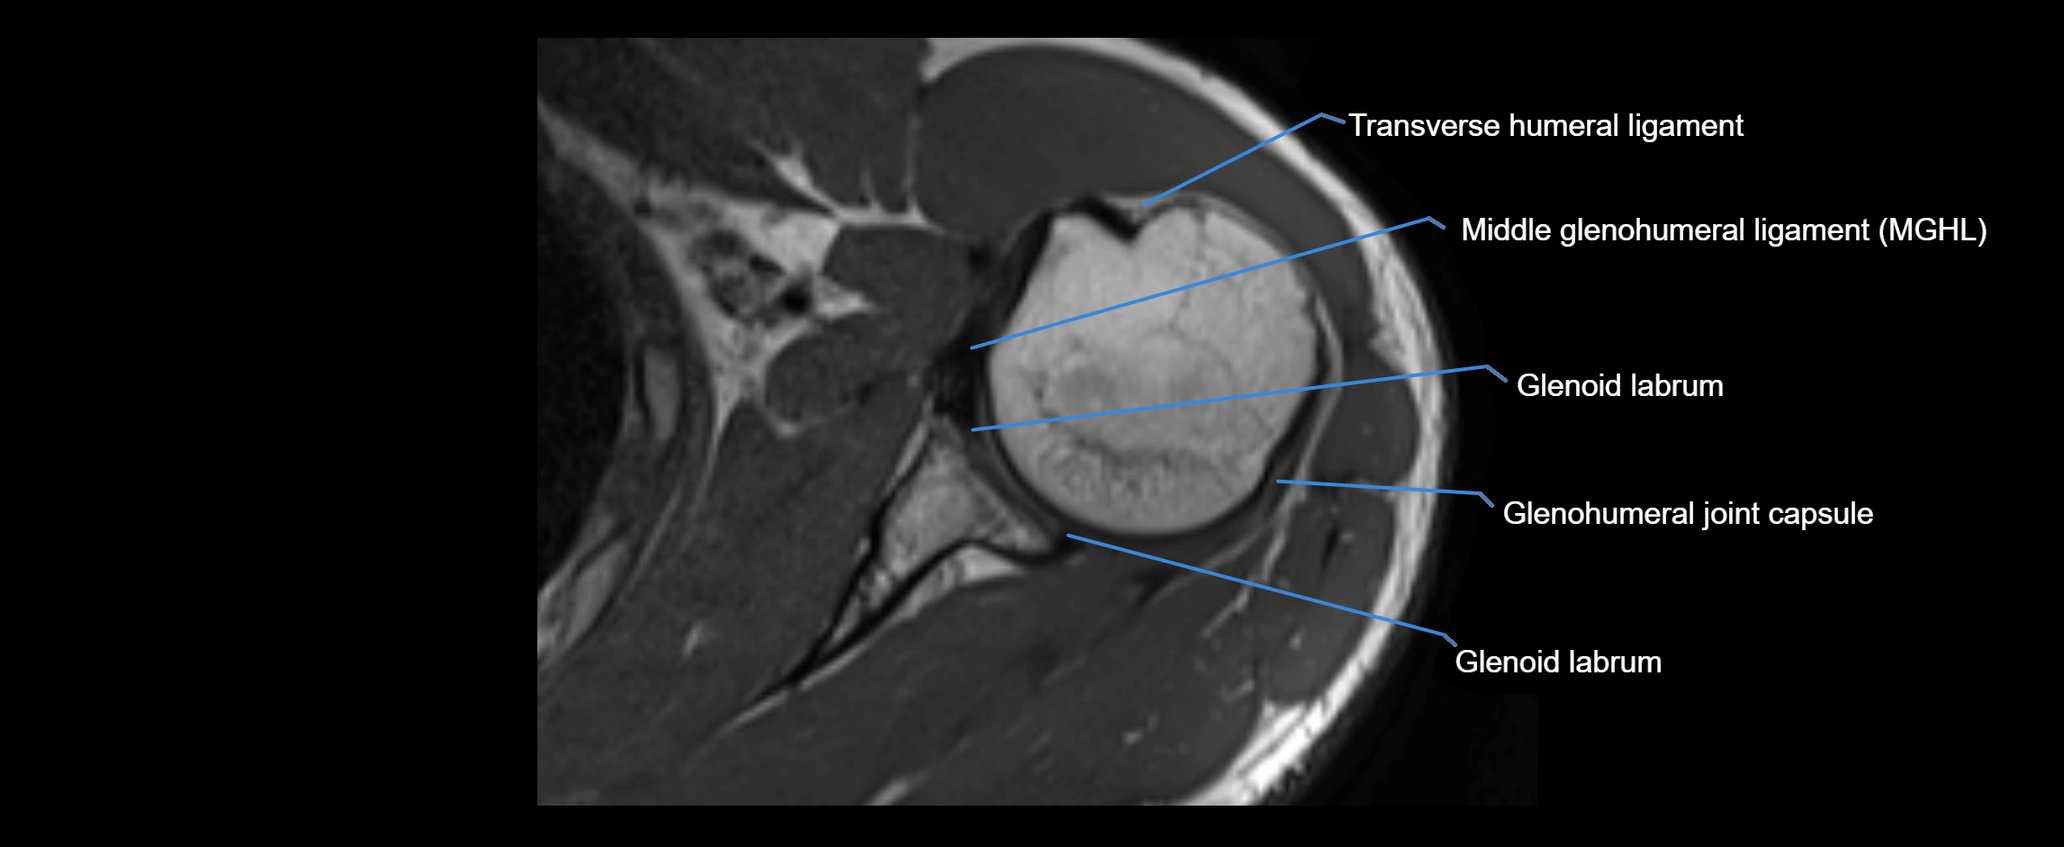

MRI images

image